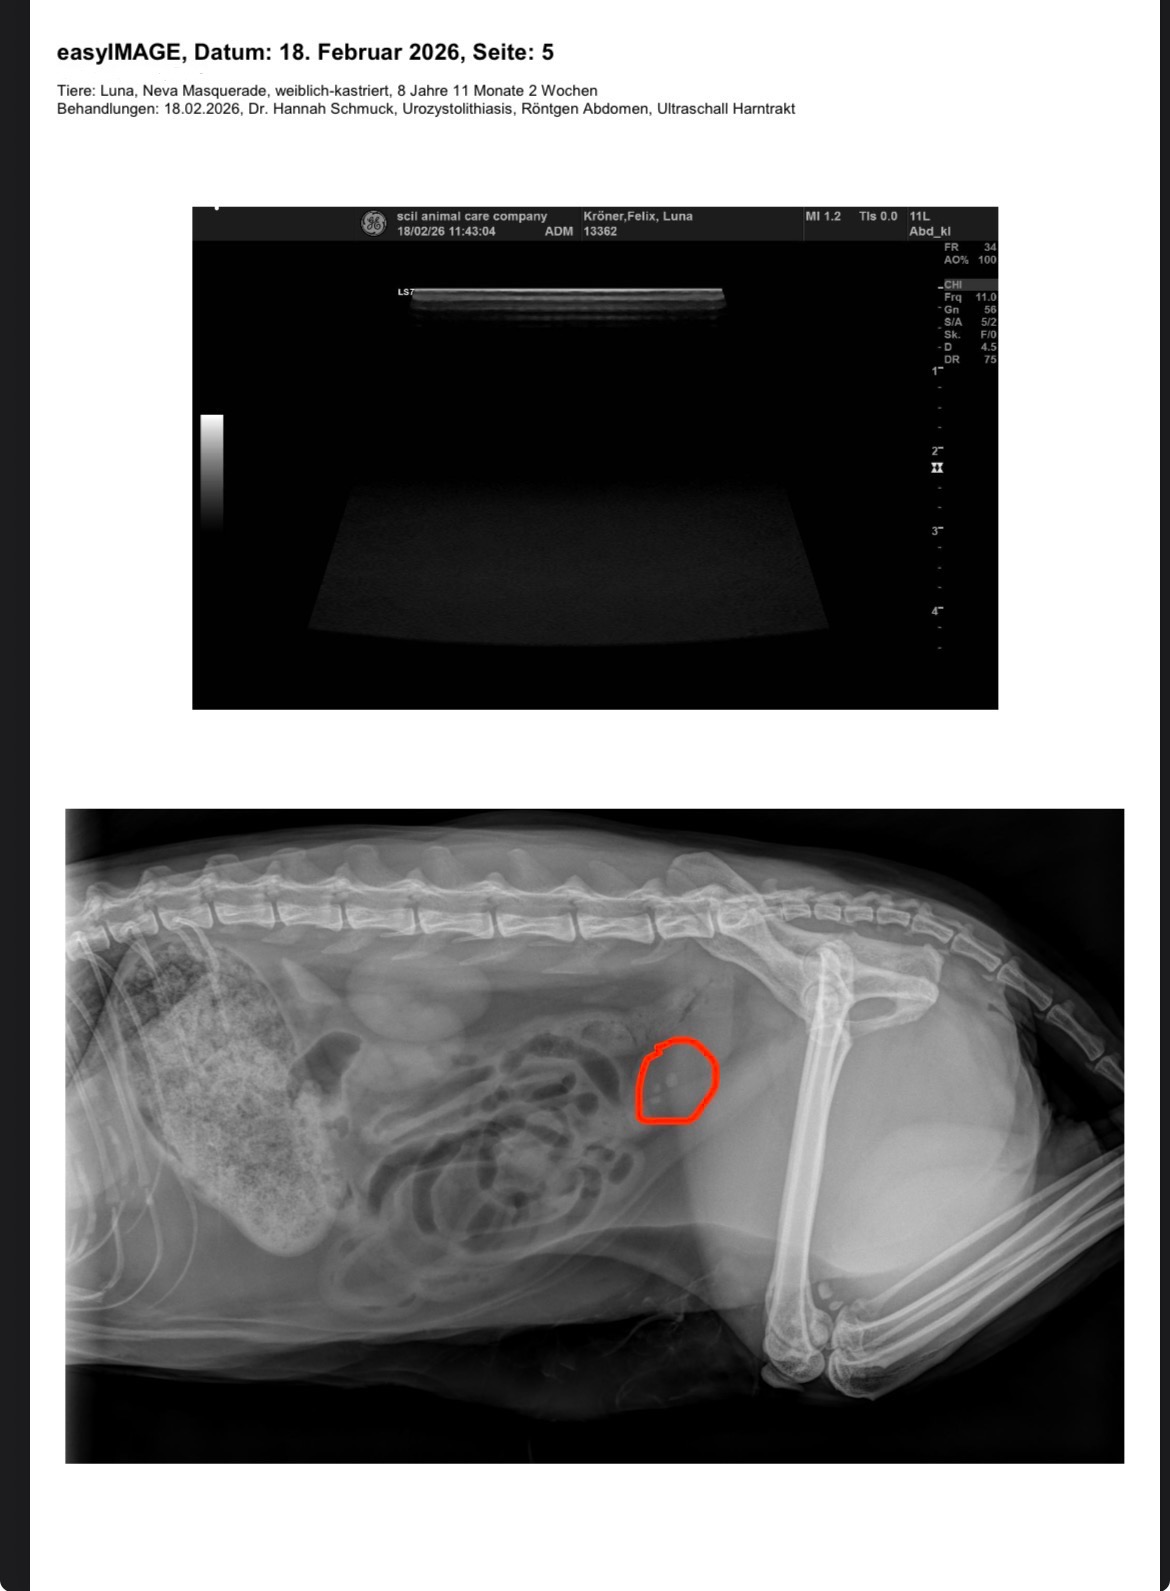

I took her to the vet for checkup fearing and hoping it wouldn’t be stones again and unfortunately the X-rays showed three stones in her bladder.

Knowing her previous symptoms 5 years ago, the size of the stones and due to the fact that she is already on specialized food, the vet says surgery again is the only way to make her comfortable again.

This will be her second surgery, and it pains me to see her going through this again. The stones present in her bladder are suspected to be oxalate crystals which are highly recurrent and not possible to dissolved through diet. She is also already on Royal Canin S/O urinary food but it seems to not be effective enough.